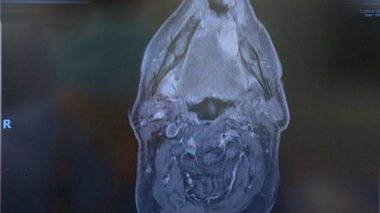

Cancer du poumon : quand un robot participe à la chirurgie